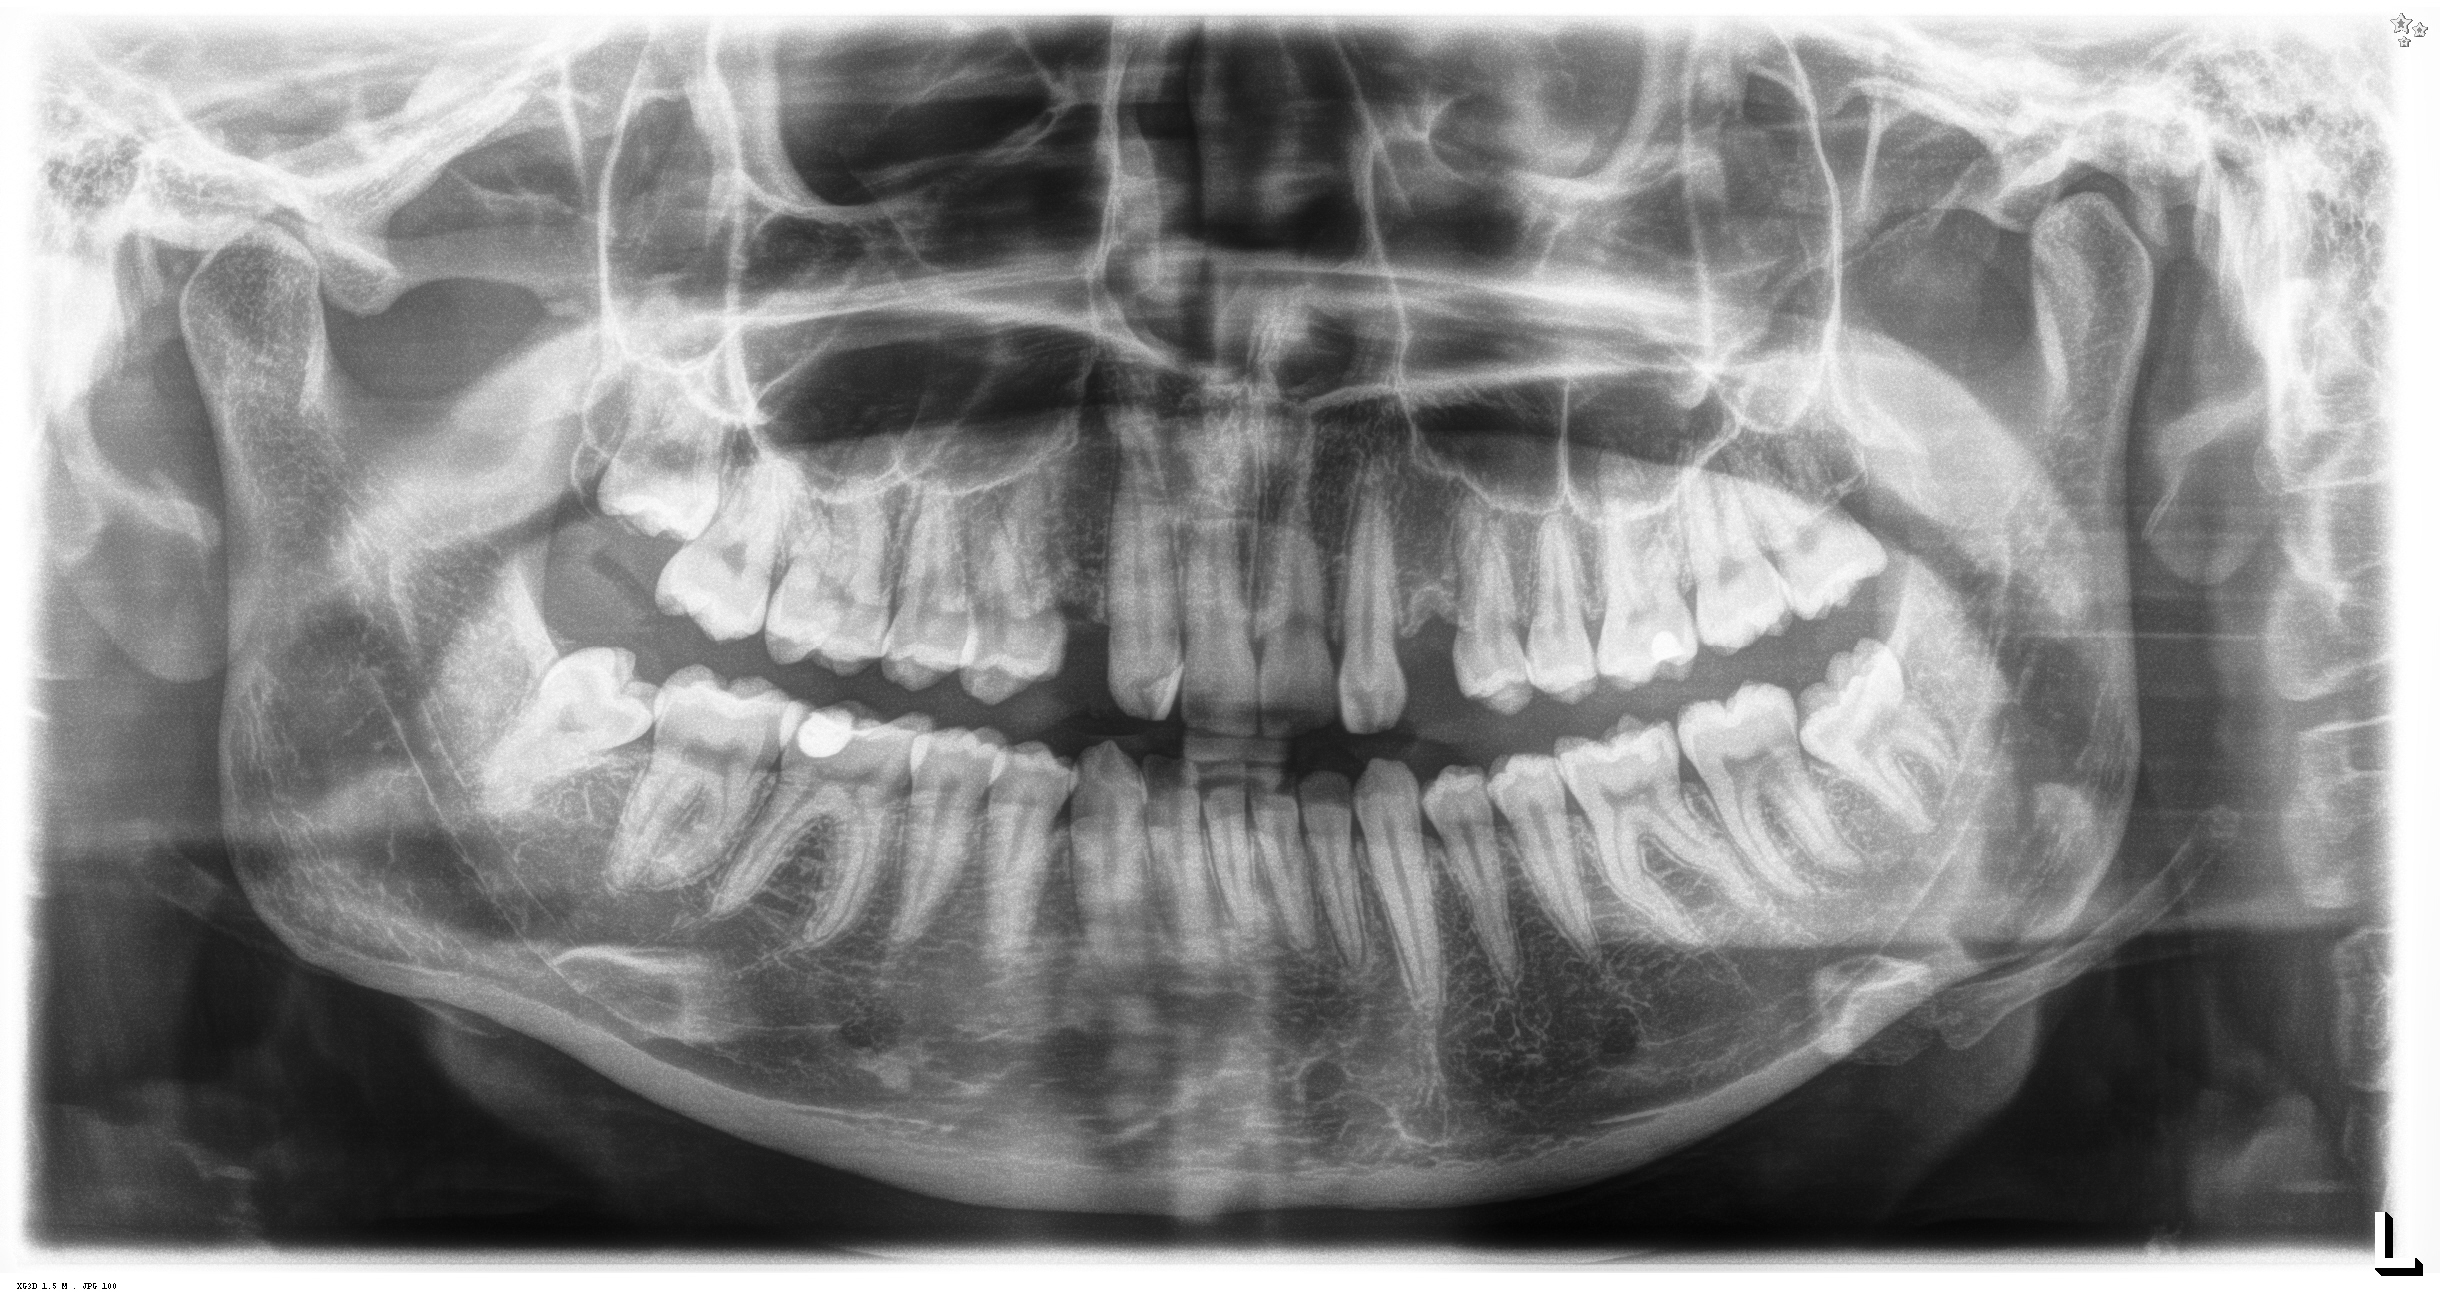

Radiologinen näkymä tilanteesta